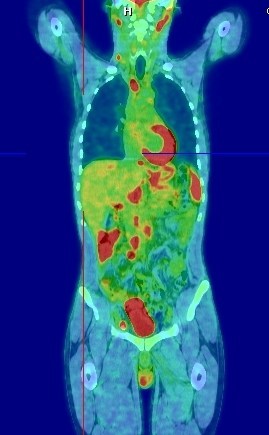

PREPARING MY PATIENT FOR F-18 FDG PET/CT STUDY